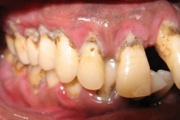

GAgP 25 aastasel suitsetaval patsiendil

GAgP 25 aastasel suitsetaval puuduliku suuhügieeniga patsiendil